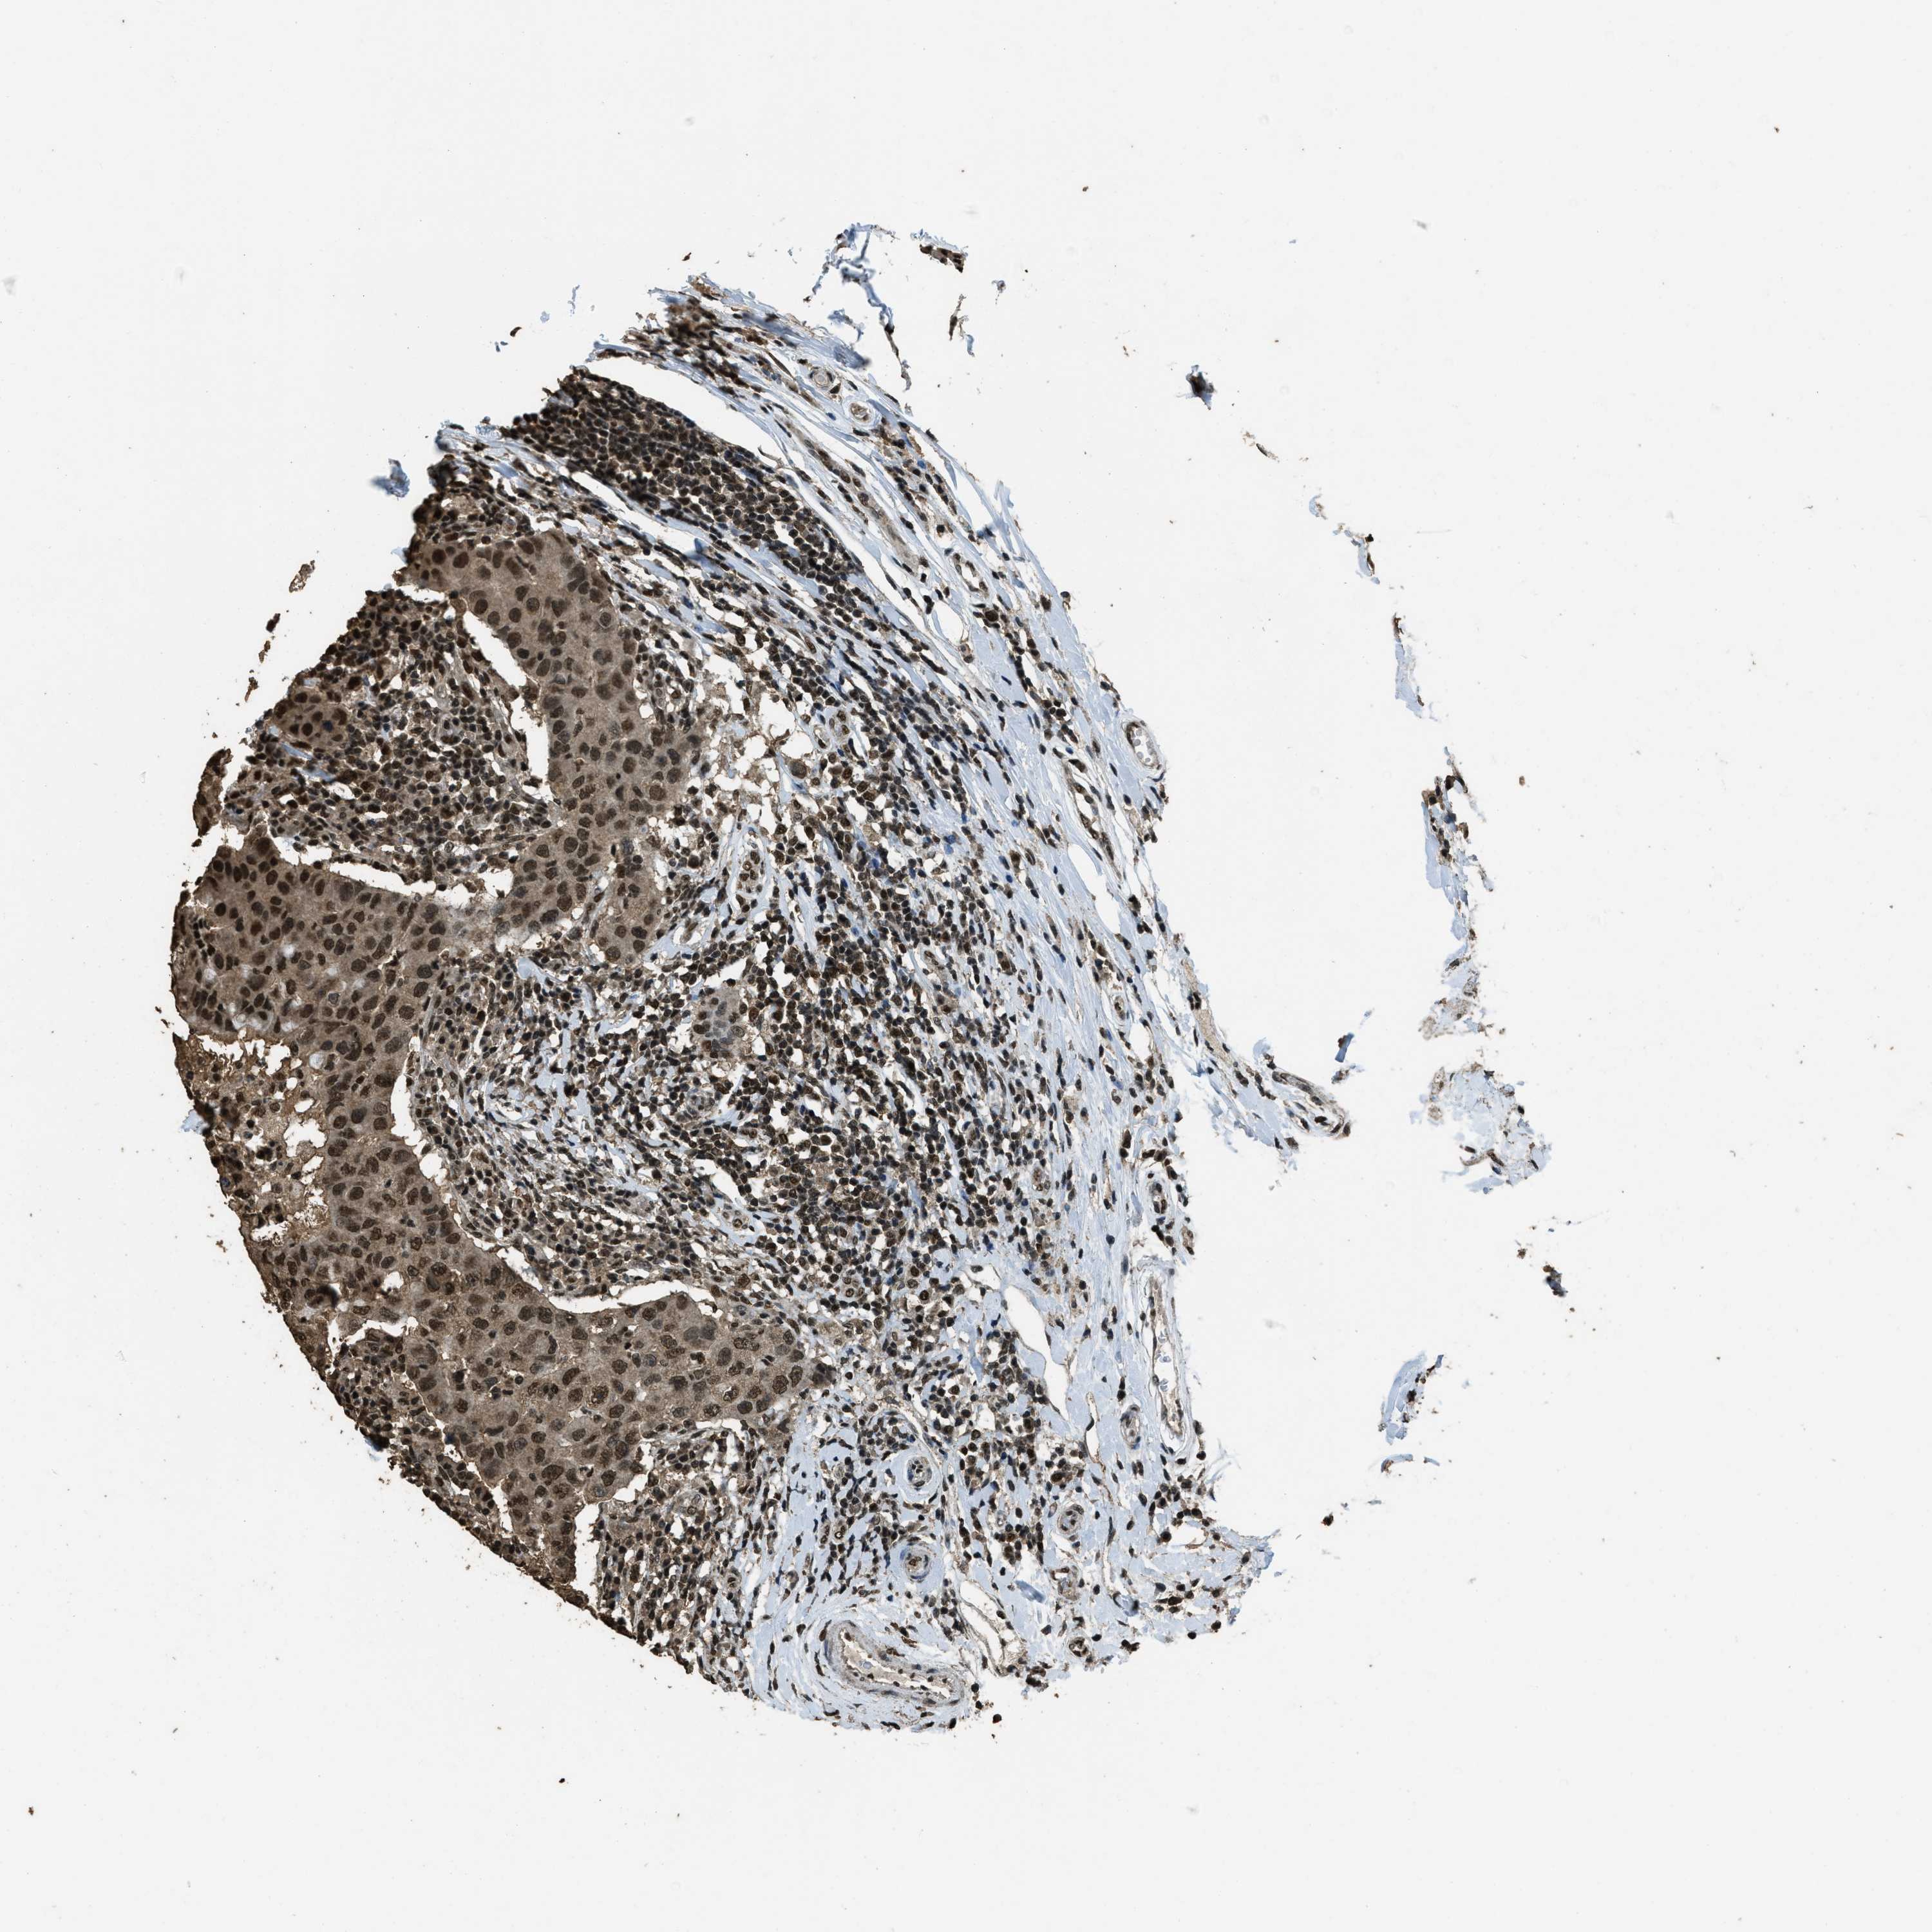

CANCER BREAST CANCER Show tissue menu

Breast cancer

Human cancer